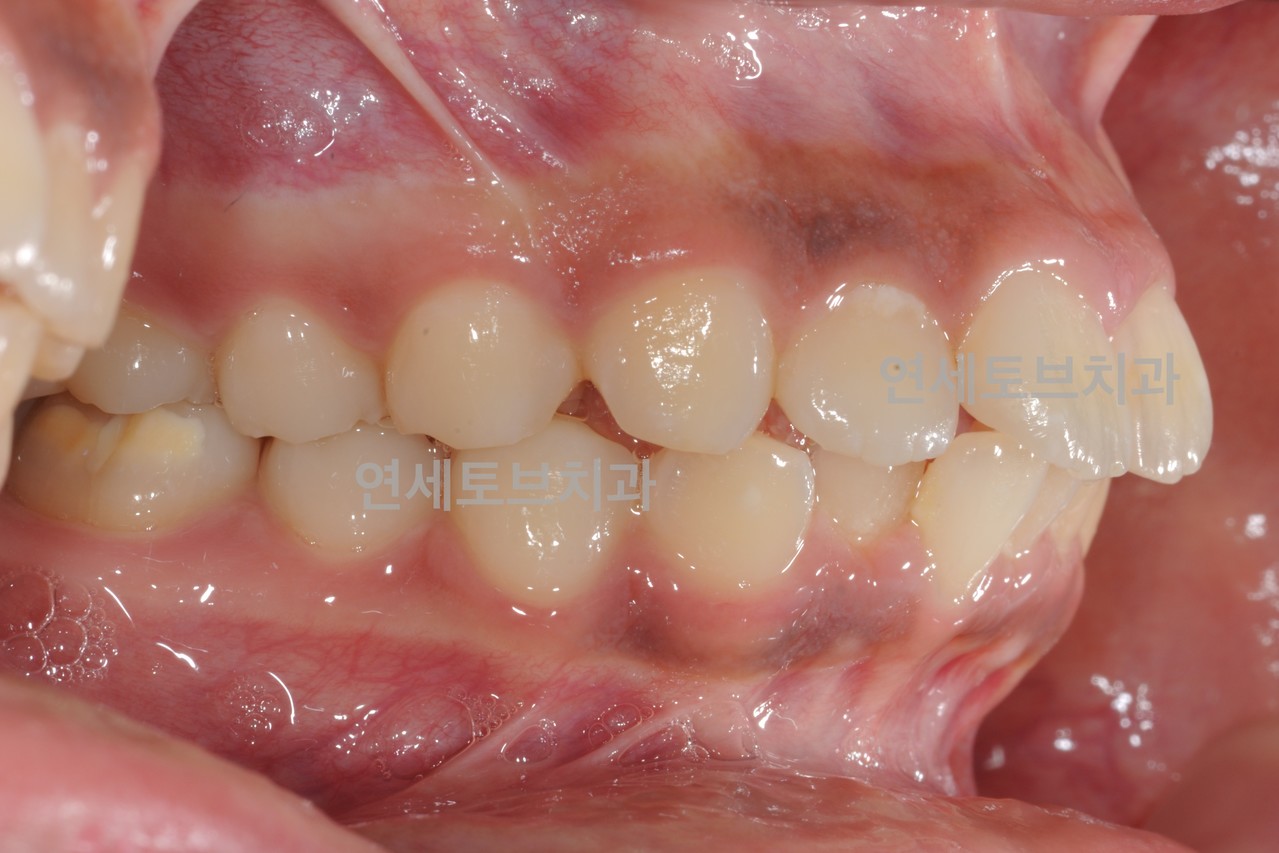

Before

돌출입은 윗니나 아랫니(또는 둘 다)가 정상적인 위치보다 앞으로 튀어나온 상태를 말합니다.

이로 인해 입술이 앞으로 돌출되어 보이고, 측면 얼굴 프로필에서 특히 두드러지게 나타납니다.

한국인을 포함한 동양인에게 비교적 흔하게 나타나는 부정교합 유형입니다.